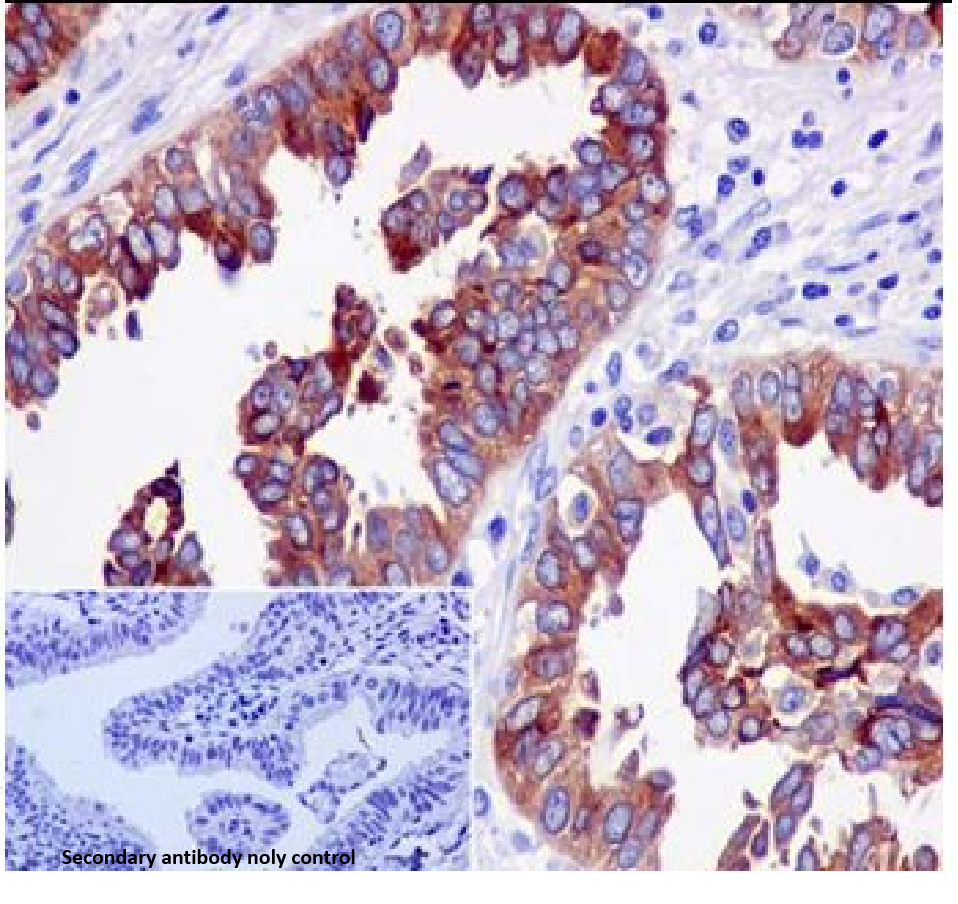

Cellular localization: cytoplasm/membrane

Tissue: paraffin section

Human epididymal protein 4 (HE4) is an acidic, small, single-signal peptide and cysteine-rich polypeptide characterized as a secreted protein that belongs to the lactic acid protein (WAP) structural domain family of proteins.HE4 is highly expressed in the trachea and salivary glands of normal humans, and is expressed in the epithelium of the female reproductive system, including the fallopian tube epithelium, endometrial glands, endocervical glands, and vestibular gonads, as well as in the epithelia of the epididymis and the vasculature of the male reproductive system. HE4 is expressed in the epithelium of the vas deferens.HE4 is highly expressed in ovarian endometrioid carcinoma and hyperdifferentiated plasma ovarian carcinoma, whereas it is expressed at lower levels in clear cell carcinoma and mucinous ovarian carcinoma.HE4 is overexpressed in pancreatic adenocarcinoma.

HE4 antibody reagents can specifically bind to HE4 molecular antigens. Immunohistochemistry kits containing HE4 antibody reagents are suitable for the auxiliary diagnosis of ovarian serous carcinoma, endometrioid carcinoma, and pancreatic cancer.